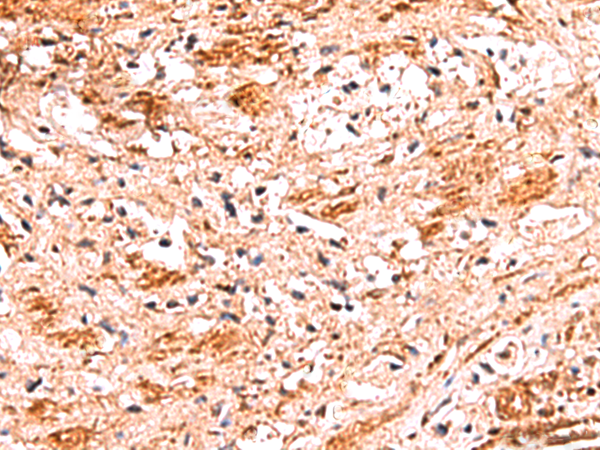

分类: 科研抗体货号: P10162别名: bA67K19.1应用: IHC反应种属: Human, Mouse